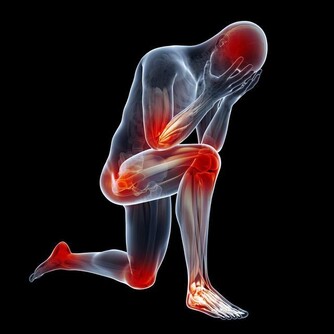

手麻與腳麻主要表現為局部刺痛、麻木或感覺異常,這可能是由於神經受到壓迫、血液循環不良或其他健康問題所引起。根據最新的健康研究,這些症狀不僅僅是短暫的不適,也可能是身體發出的緊訊,提醒我們及時關注潛在的疾病風險。

綜合上述分析,手麻與腳麻可能源自多種原因,包括神經受壓、血液循環不良、營養缺乏以及慢性疾病等。這些症狀往往是身體發出的緊訊,提示我們需更加關注日常生活中的健康狀況。透過調整生活習慣、改善飲食以及定期健康檢查,我們可以及早發現問題並採取適當措施,減少健康風險。